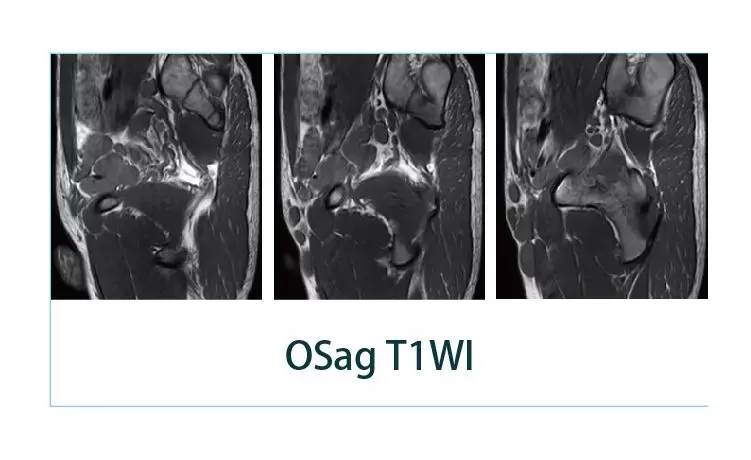

【朗润影像档案】磁共振影像病例分享(编号20190426)

【朗润影像档案】磁共振影像病例分享(编号20190419)

【朗润影像档案】磁共振影像病例分享(编号20190412)

【朗润影像档案】磁共振影像病例分享(编号20190405)